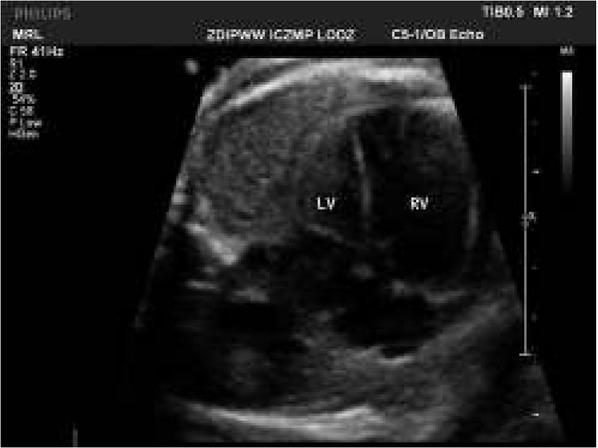

Fig. 2